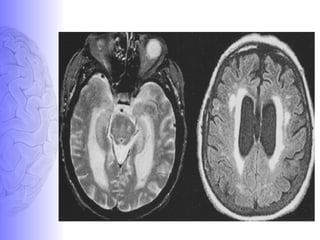

Normal ALZHEIMER’S DISEASE

ALZHEIMER’S DISEASENORMAL

2. DEMENTIA WITH LEWY BODIES

• It is characterized by

presence of lewy bodies in the

cortical neurons on histology.

• It is 2nd

/ 3rd

most common

cause of dementia in elderly.

• To date, no MRI features

have been identified that to

characterize DLB.

• “THE ABSENCE OF

SIGNIFICANT MEDIAL

TEMPORAL LOBE

ATROPHY” in a elderly

demented patient suggests

DLB etiology rather than AD

etiology.